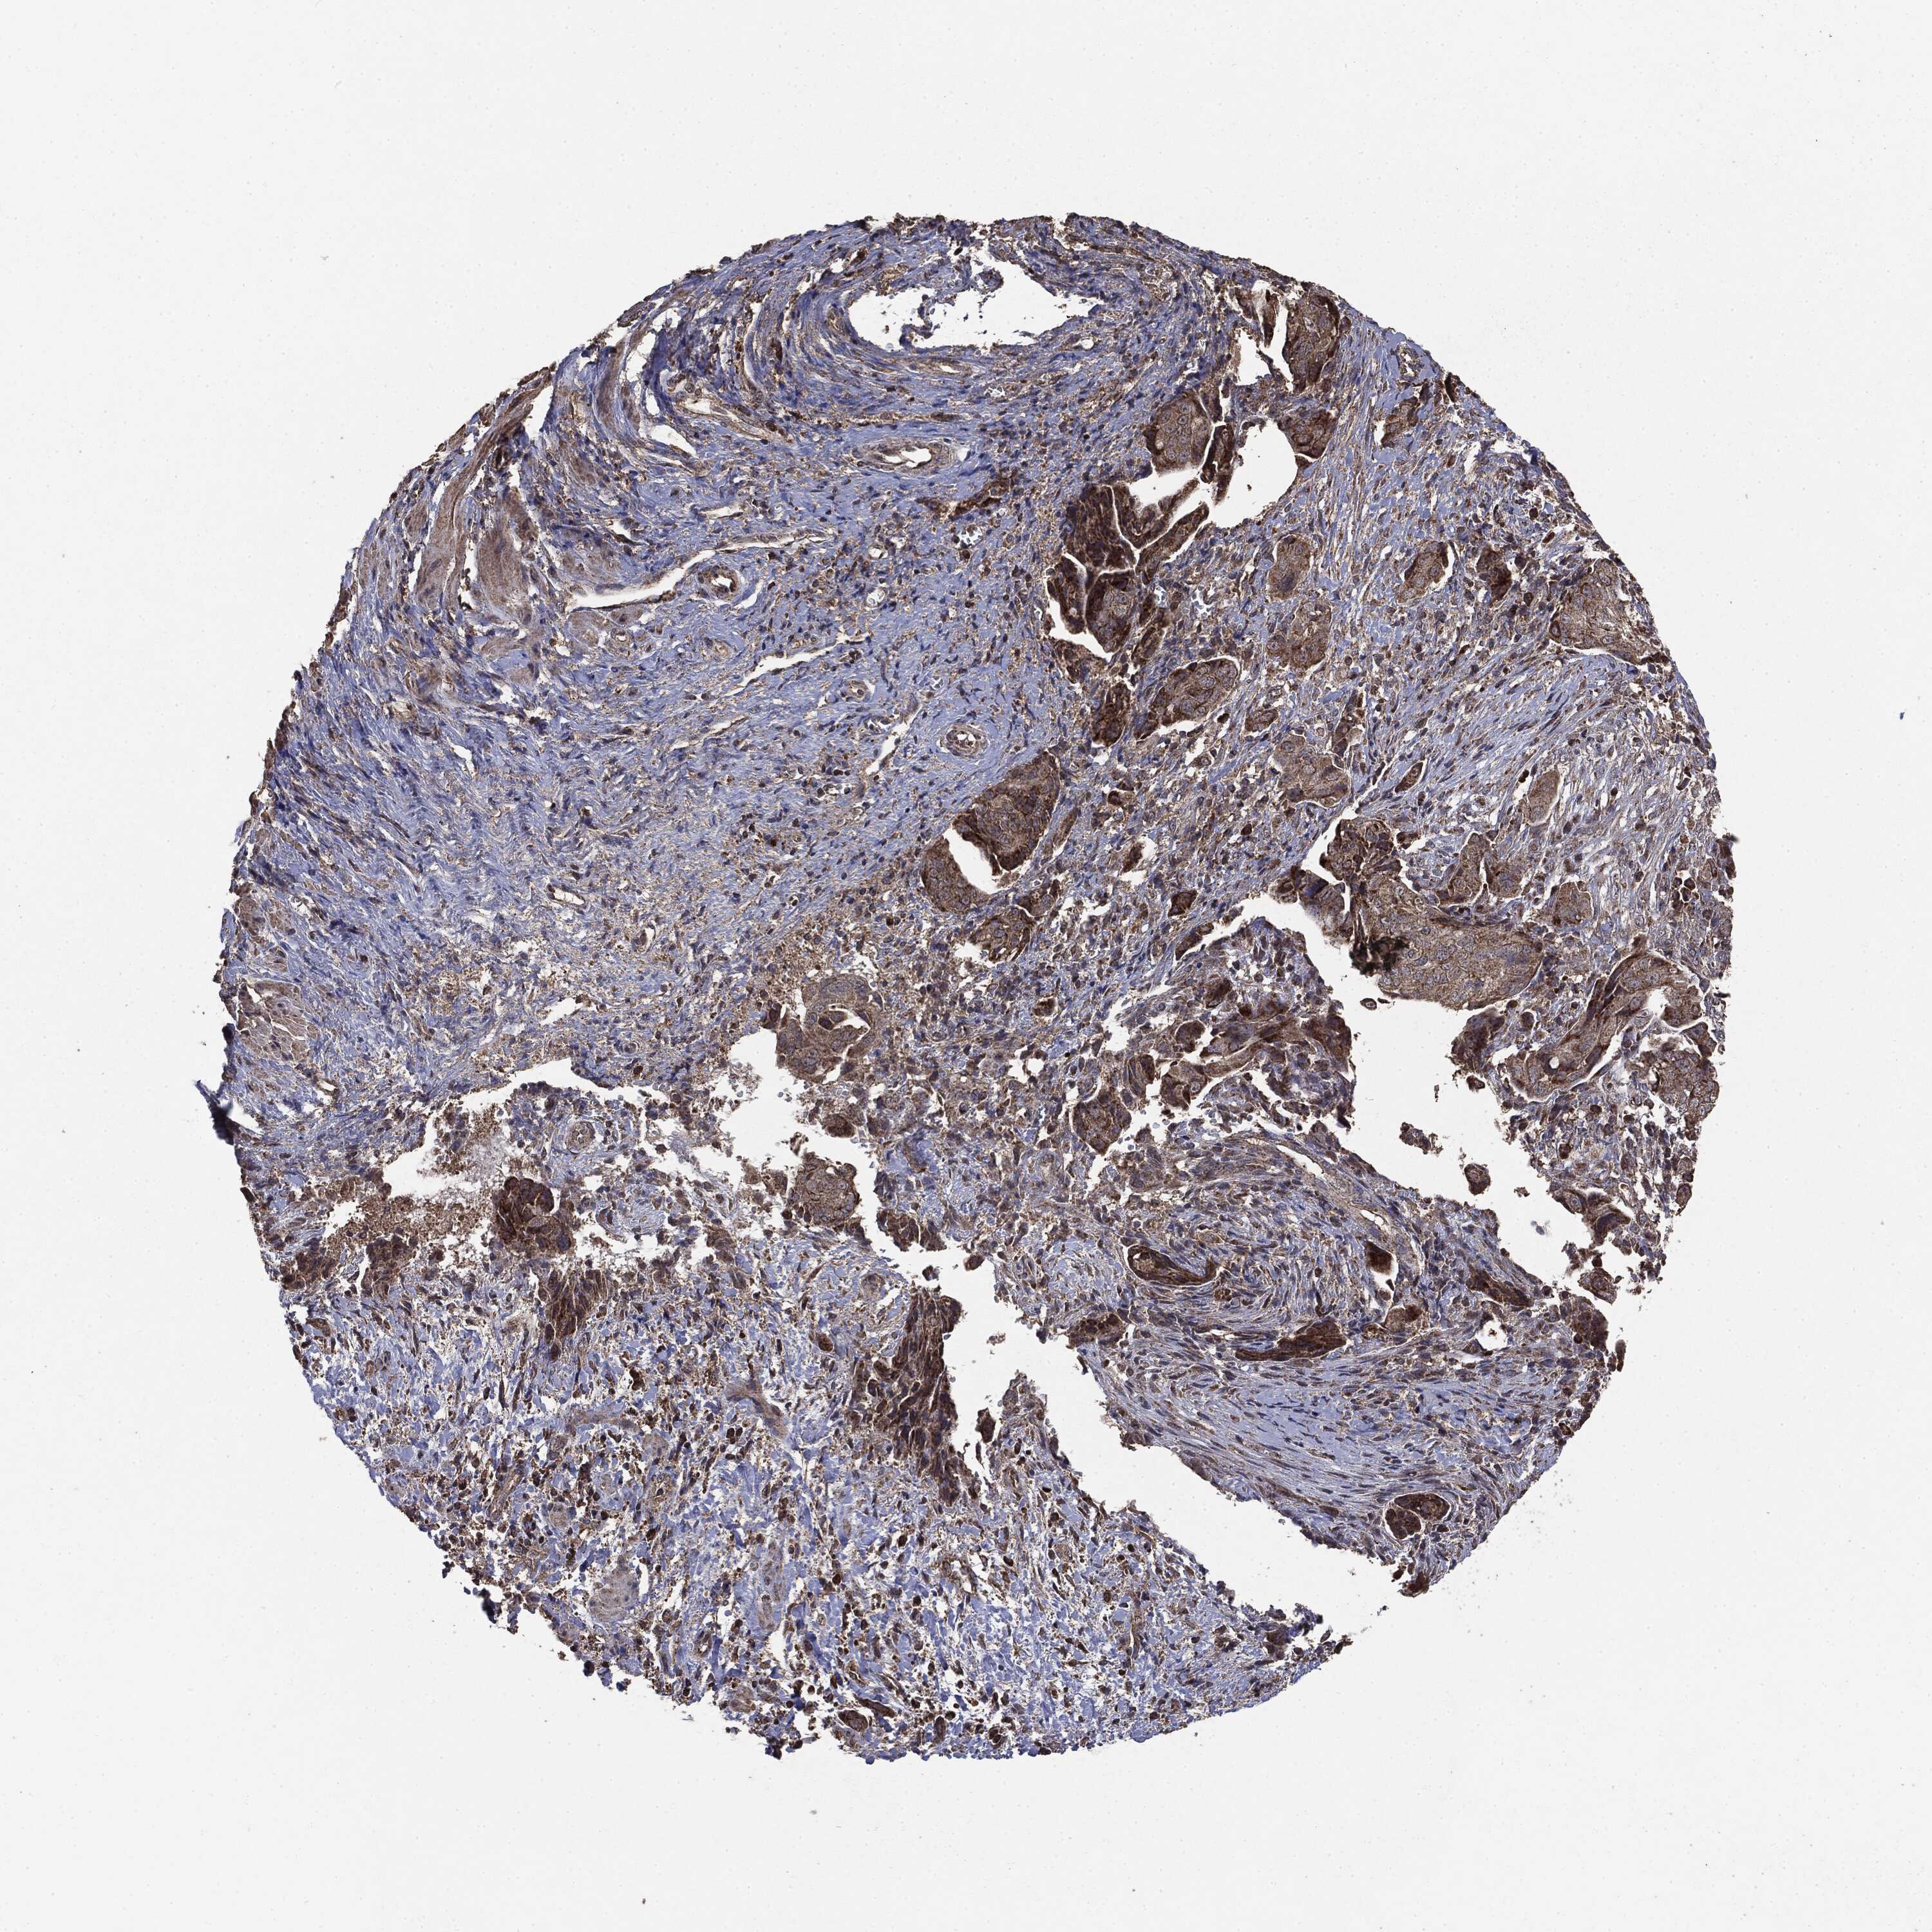

OVARIAN CANCER - Protein expressioni

A mouse-over function shows sample information and annotation data. Click on an image to view it in a full screen mode. Samples can be filtered based on level of antibody staining by selecting one or several of the following categories: high, medium, low and not detected. The assay and annotation is described here.

Note that samples used for immunohistochemistry by the Human Protein Atlas do not correspond to samples in the TCGA dataset.

Antibody stainingi

Antibody staining in the annotated cell types in the current human tissue is reported as not detected, low, medium, or high, based on conventional immunohistochemistry profiling in selected tissues. This score is based on the combination of the staining intensity and fraction of stained cells.

Each image is clickable and will lead to virtual microscopy that enables deeper exploration of all samples and also displays staining intensity scores, fraction scores and subcellular localization as well as patient and tissue information for each sample.

CAB069425